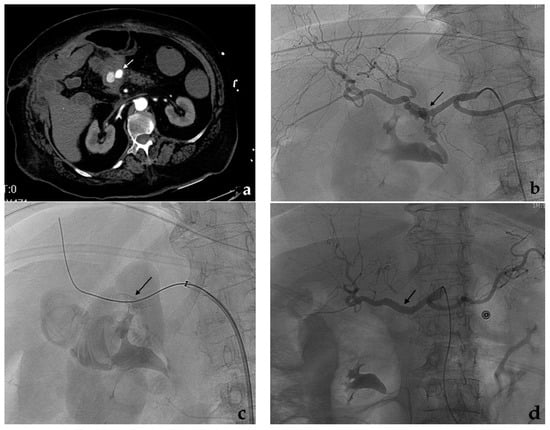

3.2. Stent-Assisted Coil Embolization

- Wei, X.; Sun, Y.; Wu, Y.; Li, Z.; Zhu, J.; Zhao, Z.; Feng, R.; Jing, Z. Management of wide-based renal artery aneurysms using non covered stent-assisted coil embolization. J. Vasc. Surg. 2017, 66, 850–857. [Google Scholar] [CrossRef]

- Secco, G.; Chevallier, O.; Falvo, N.; Guillen, K.; Comby, P.O.; Mousson, C.; Majbri, N.; Midulla, M.; Loffroy, R. Packing technique with or without remodeling for endovascular coil embolization of renal artery aneurysms: Safety, efficacy and mid-term outcomes. J. Clin. Med. 2021, 10, 326. [Google Scholar] [CrossRef]

- Ma, T.; He, Y.; Zhong, W.; Luo, G.; Li, Q.; Wang, Z.; Zhang, H.; Wu, Z.; Qiu, C. Mid-term results of coil embolization alone or stent-assisted coil embolization for renal artery aneurysms. Ann. Vasc. Surg. 2021. [Google Scholar] [CrossRef]

- Bracale, U.M.; Narese, D.; Ficarelli, I.; De Laurentis, M.; Spalla, F.; Dinoto, E.; Vitale, G.; Solari, D.; Bajardi, G.; Pecoraro, F. Stent-assisted detachable coil embolization of wide-necked renal artery aneurysms. Diagn. Interv. Radiol. 2017, 23, 77–80. [Google Scholar] [CrossRef] [PubMed]